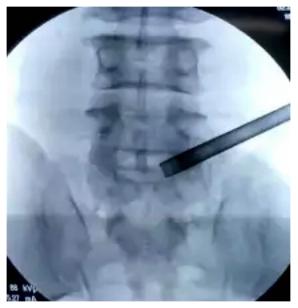

椎间孔镜手术

术者

唐都医院脊柱神经外科王鹏教授

术中

患者就诊时腰部和下肢疼痛不适等症状消失,无其他并发症或不适。